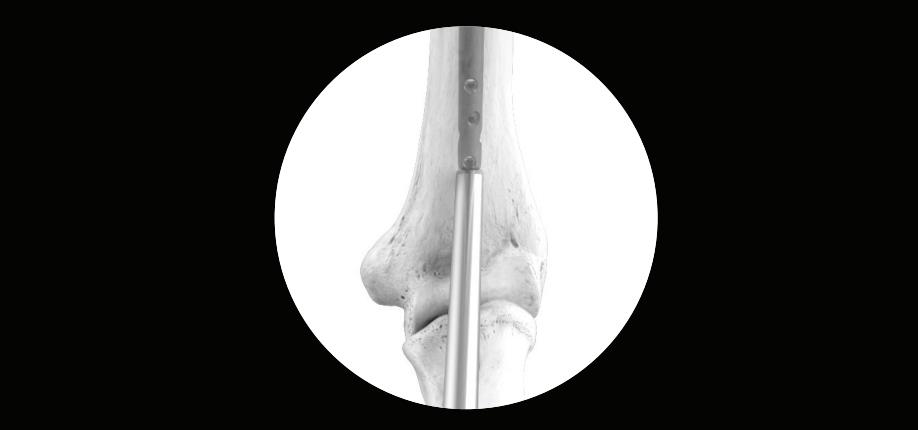

• guide wire

• insert the ball tip guide wire 2.5 x 800mm

• advance the Ball Tip Guide Wire through the fracture site and to the desired insertion depth

• insert the nail by hand over the Smooth Tip Guide Wire and into the entry site of the proximal humerus

• advance the nail past the fracture site

• insert the nail so that it is countersunk below the articular surface

• do not leave the nail proud as this could damage the joint surface

• remove the guide wire once the nail is appropriately positioned